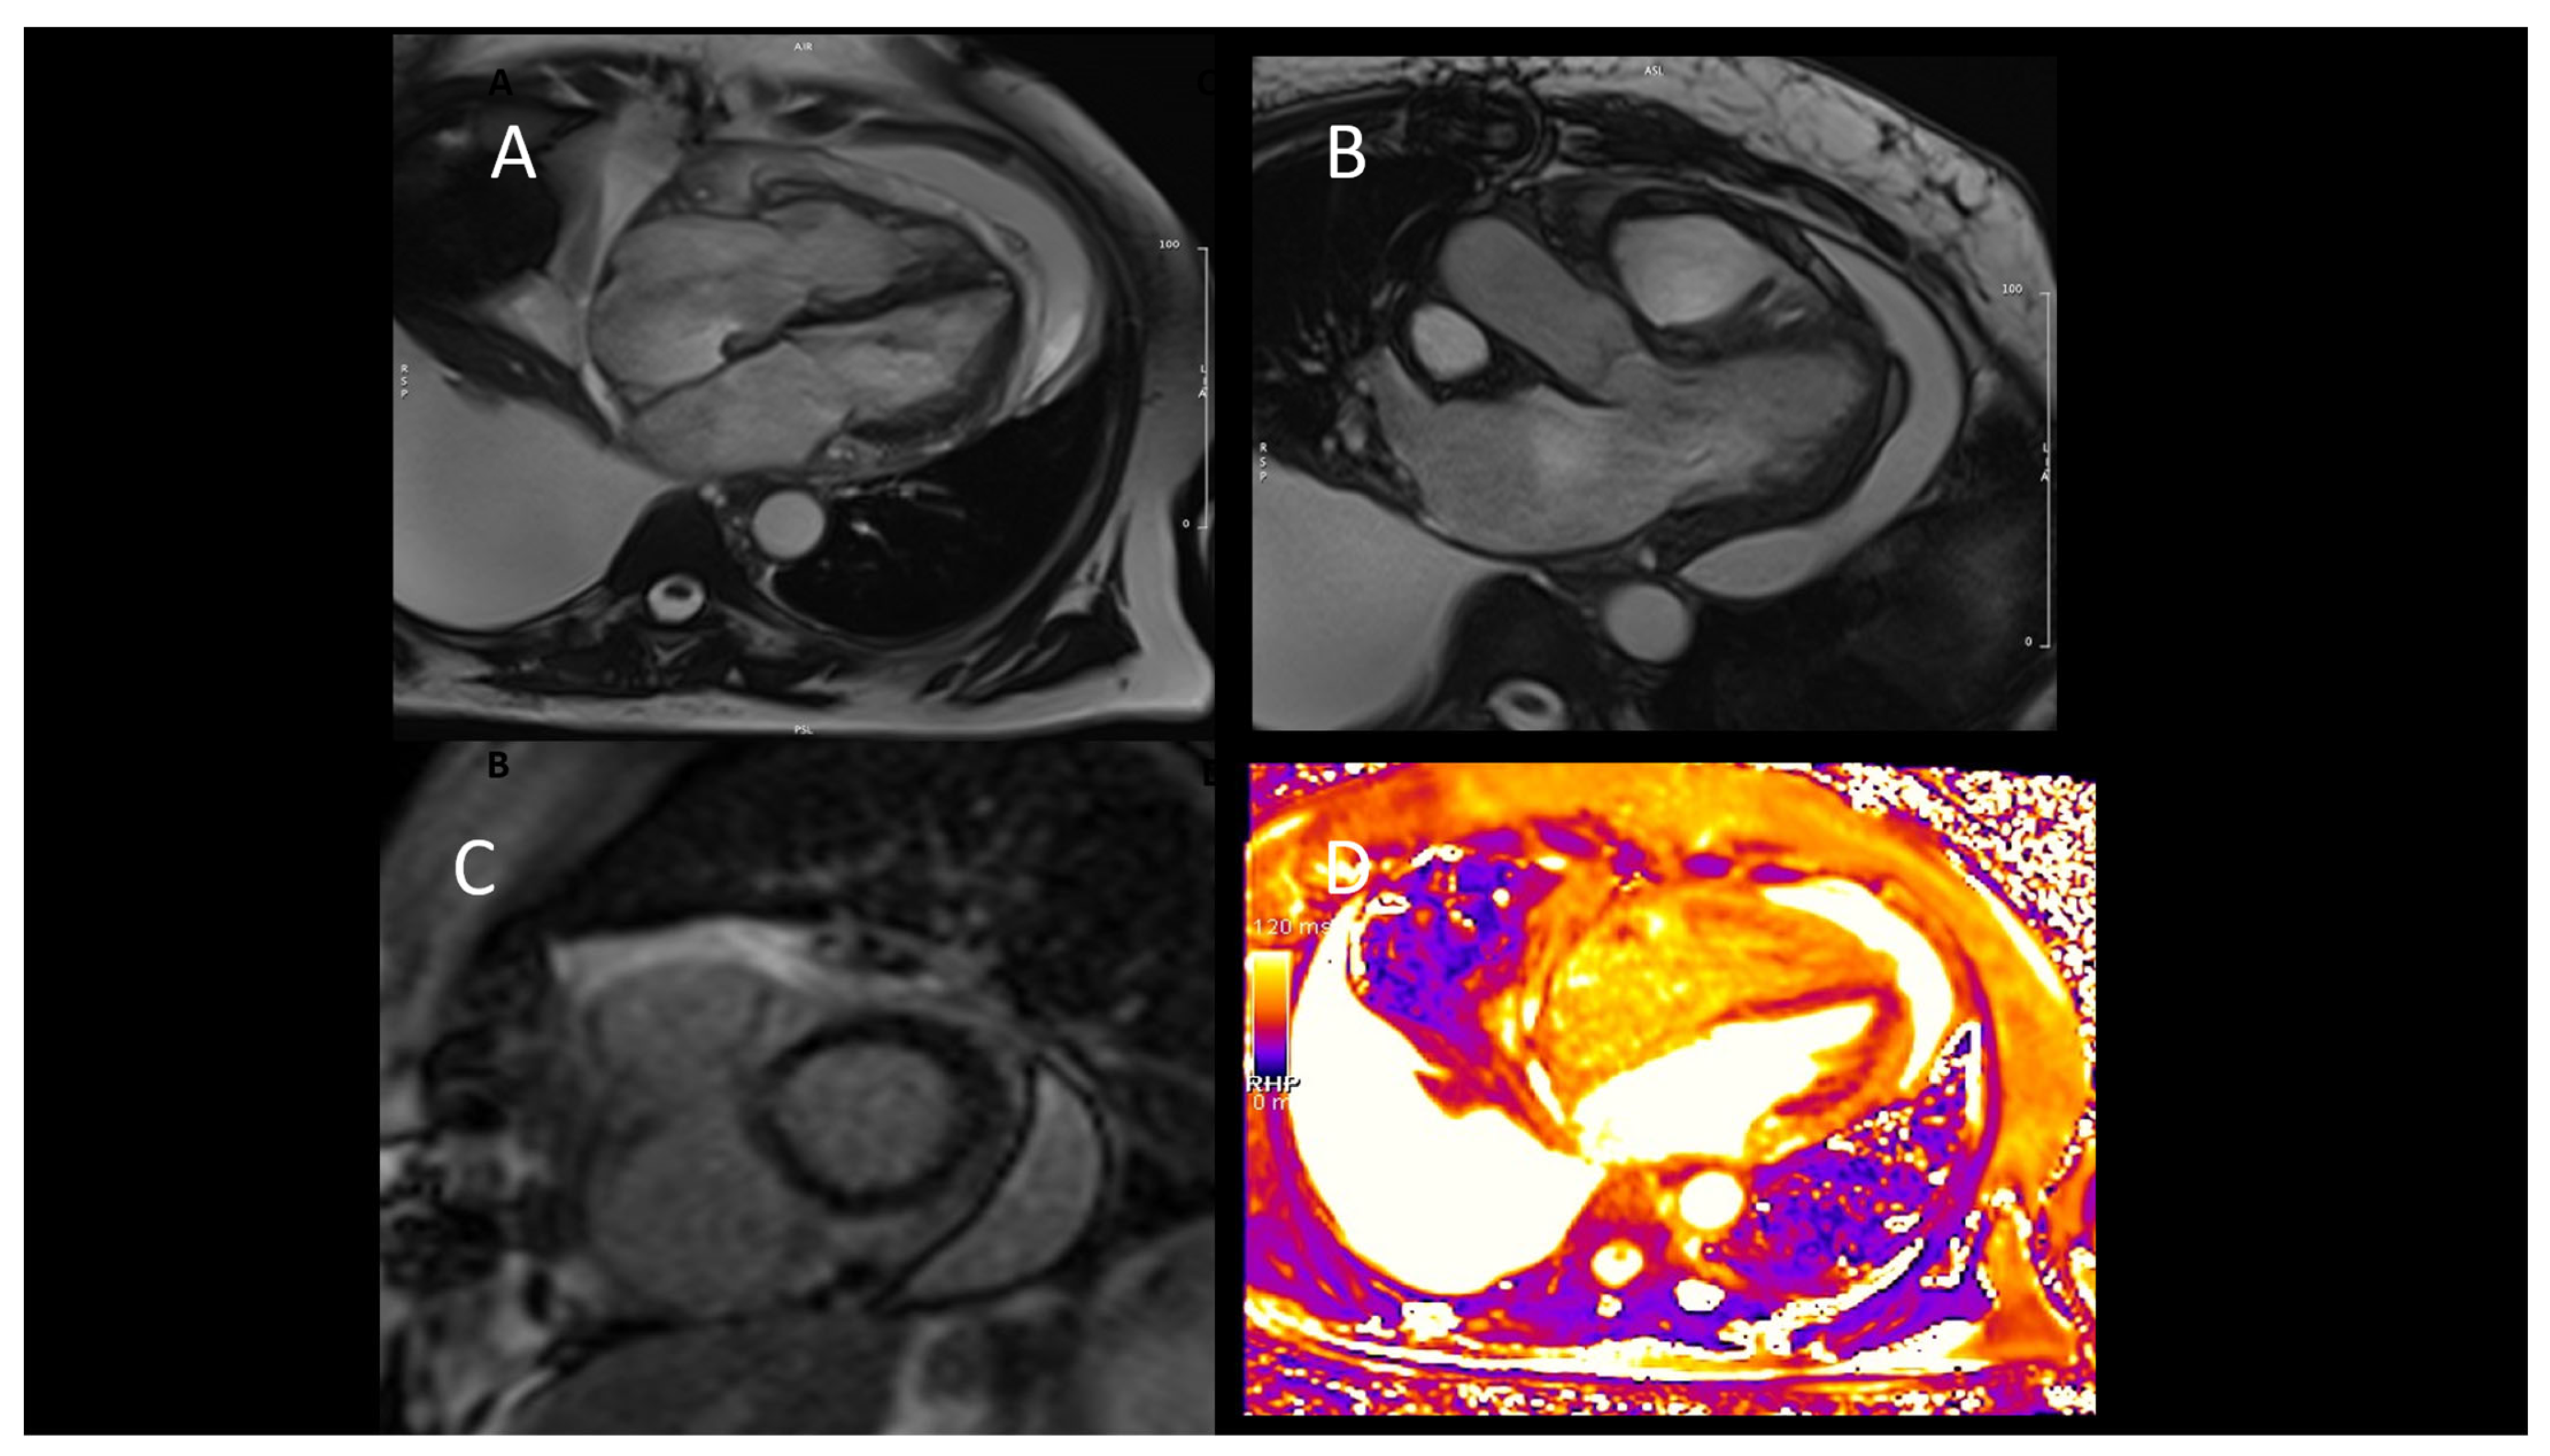

2.4.2. Cardiac Magnetic Resonance

- Sade, L.E.; Hazirolan, T.; Kozan, H.; Ozdemir, H.; Hayran, M.; Eroglu, S.; Pirat, B.; Sezgin, A.; Muderrisoglu, H. T1 mapping by cardiac magnetic resonance and multidimensional speckle-tracking strain by echocardiography for the detection of acute cellular rejection in cardiac allograft recipients. JACC Cardiovasc. Imaging 2019, 12 Pt 2, 1601–1614. [Google Scholar] [CrossRef]

- Vermes, E.; Pantaléon, C.; Auvet, A.; Cazeneuve, N.; Machet, M.C.; Delhommais, A.; Bourguignon, T.; Aupart, M.; Brunereau, L. Cardiovascular magnetic resonance in heart transplant patients: Diagnostic value of quantitative tissue markers: T2 mapping and extracellular volume fraction, for acute rejection diagnosis. J. Cardiovasc. Magn. Reson. 2018, 20, 59. [Google Scholar] [CrossRef] [PubMed]

- Erbel, C.; Mukhammadaminova, N.; Gleissner, C.A.; Osman, N.F.; Hofmann, N.P.; Steuer, C.; Akhavanpoor, M.; Wangler, S.; Celik, S.; Doesch, A.O.; et al. Myocardial Perfusion Reserve and Strain-Encoded CMR for Evaluation of Cardiac Allograft Microvasculopathy. JACC Cardiovasc. Imaging 2016, 9, 255–266. [Google Scholar] [CrossRef]

- Dolan, R.S.; Rahsepar, A.A.; Blaisdell, J.; Suwa, K.; Ghafourian, K.; Wilcox, J.E.; Khan, S.S.; Vorovich, E.E.; Rich, J.D.; Anderson, A.S.; et al. Multiparametric Cardiac Magnetic Resonance Imaging Can Detect Acute Cardiac Allograft Rejection After Heart Transplantation. JACC Cardiovasc. Imaging 2019, 12, 1632–1641. [Google Scholar] [CrossRef]